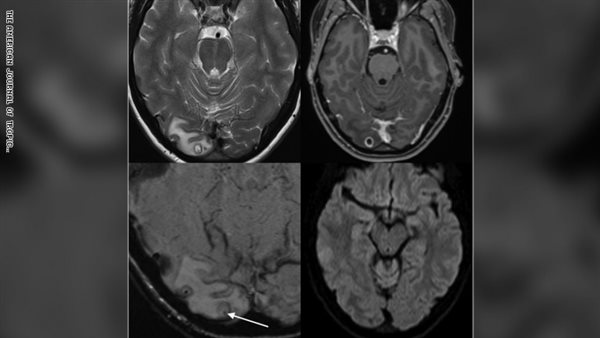

وبعد فحص كبير من الأطباء، وبأستخدام جلسة تصوير بالرنين المغناطيسي لدماغها، أعتقدوا وجود ورم، وعند إقامة عملية لأزالة الورم أكتشفوا أنه كيس مليء بيرقات دودة شريطية.